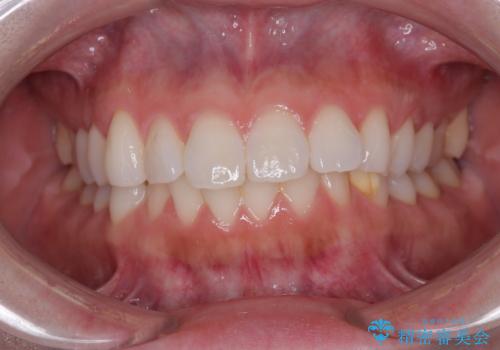

- 前歯の突出感を気にして来院された患者様です。

左右ともに奥歯の咬み合わせが上顎前突となっており、上顎前歯が飛び出している状態でした。

奥歯の咬み合わせはしっかりと改善され、前歯の突出感も改善されました。